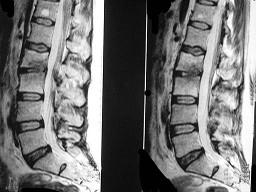

问题 男,53岁,高热,寒战,背痛半月余,请结合影像学检查选出最可能的诊断 ( )

选项 A、强直性脊柱炎 B、椎体压缩骨折 C、脊柱骨髓炎 D、脊柱结核 E、脊柱转移瘤

答案 C